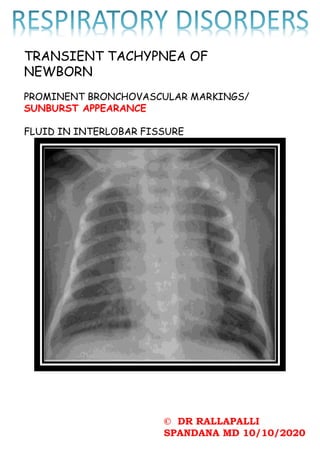

TRANSIENT TACHYPNEA OF

NEWBORN

PROMINENT BRONCHOVASCULAR MARKINGS/

SUNBURST APPEARANCE

FLUID IN INTERLOBAR FISSURE